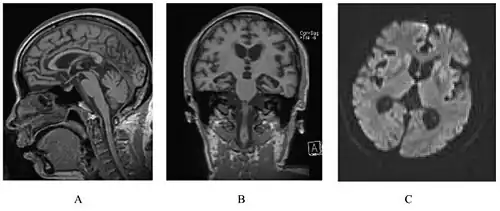

A person with inherited prion disease has cerebellar atrophy. This is quite typical of GSS. | |